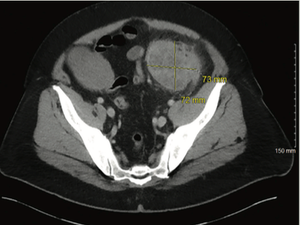

ByMehmet Sitki Copur, MD, FACP,Caleb W. Schroeder, MD,Quan Ly, MD,Whitney Wedel, MD,Jacqueline R. Kelly, MD, MSc,Paul Rodriguez, MD,Soe Min Tun, MD, MBA, MSc,Nicholas Lintel, MD,Adam J. Horn, MD,Bronson Riley, CGC This case presents a patient with locally advanced, unresectable, mismatch repair–deficient sigmoid colon cancer who was treated with neoadjuvant chemoimmunotherapy followed by surgical resection leading to a complete pathologic response after preoperative systemic chemoimmunotherapy.